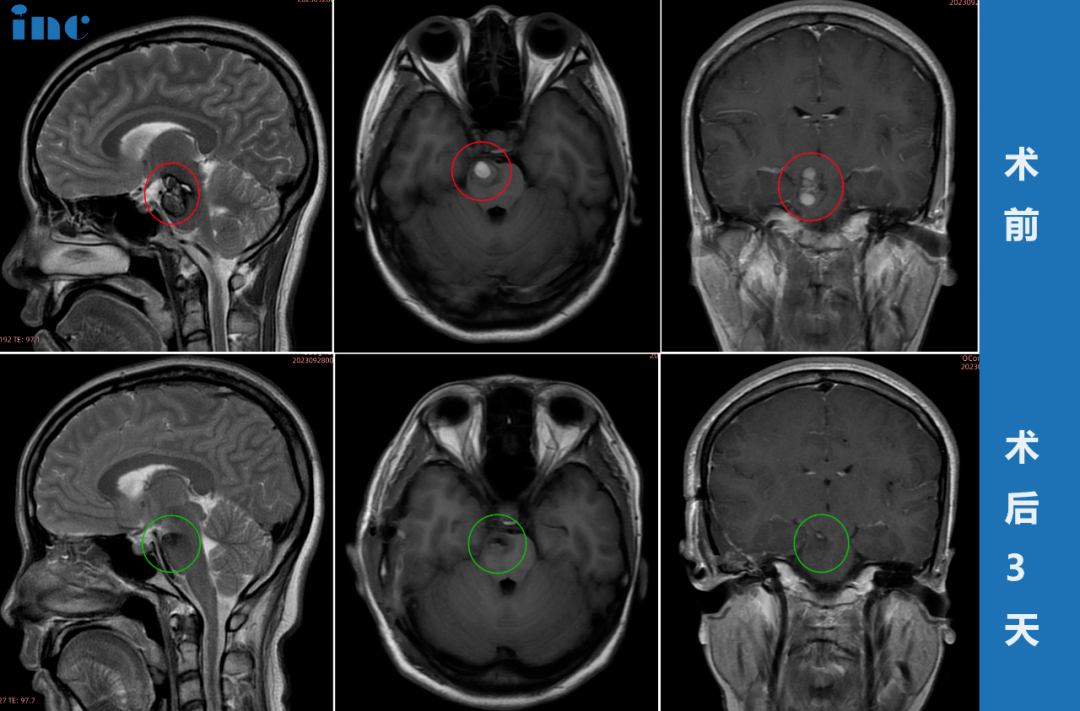

▼36歲女性-松果體區(qū)腫瘤

36歲女性-松果體區(qū)腫瘤